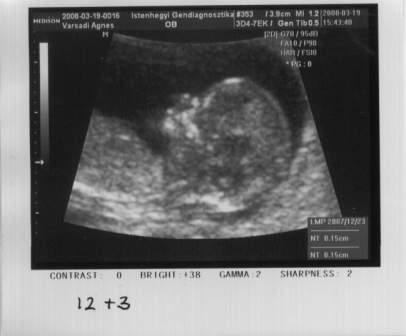

Nálunk minden ok. Ma voltam NST-n. Azt mondták, hogy lehet, hogy épp fordulóban van, mert nem rendesen farvégűen fekszik, hanem, mint egy kisbéka, kicsit keresztben. Valószínűleg helye még van, mert akkorákat tud rúgni, boxolni, hogy kilyukasztja a pocakomat. Még mindig nagyon sokat csuklik. Viszont sajnos el kezdett dagadni a lábam, "kicsit" vizes. És ami a legrosszabb, hogy alig tudok aludni a gyomorsavam miatt, ami már napközben is gondot okoz, így vajas pirítóson, és kakaón, tejen élünk.

Tojik Klári baba a fejemre. Nem igazán fordul. Rugdal, boxol, de fordulni azt már nem.